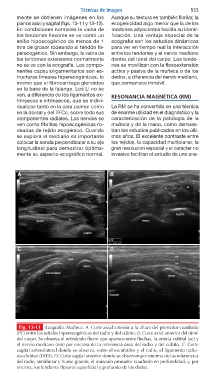

Fig. 13-11 Ecografía. Muñeca. A: Corte axial anterior a la altura del pronador cuadrado

(PC) entre las señales hiperecogénicas del radio y del cúbito. B: Corte axial anterior del túnel

del carpo. Se observa el retináculo flexor que aparece entre flechas, la arteria cubital (ac) y

el nervio mediano (nm) por encima de la referencia ósea del radio y del cúbito. C: Corte

sagital anterolateral donde se observa, entre el escafoides y el radio, el ligamento radio-

escafoideo (LRES). D: Corte sagital anterior donde se observan por encima de las referencias

del radio, semilunar y hueso grande, el músculo pronador cuadrado en profundidad, y, por

encima, los tendones flexores superficial y profundo de los dedos.